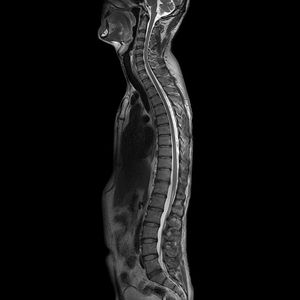

Whole spine T2 PROPELLER Sagittal. GE Discovery MR750w 3.0 Tesla. Courtesy of @gehealthcare